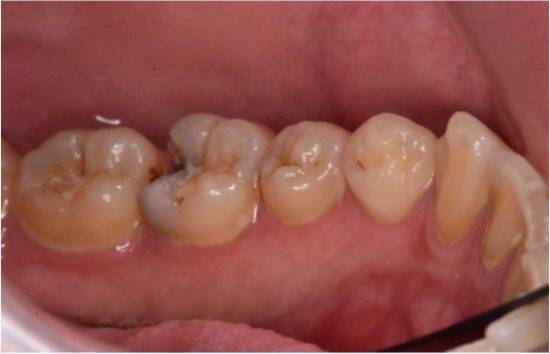

飲食をすると、口内は一時的に酸性に傾きます。この状態が長く続くと、歯の表面では脱灰(歯が溶け出す現象)が進みやすくなり、むし歯のリスクが高まります。

この組み合わせにより、むし歯菌・歯周病菌が活発になり、歯の表面(エナメル質)が弱り、むし歯だけでなく口臭や歯茎トラブルも起こりやすくなります。